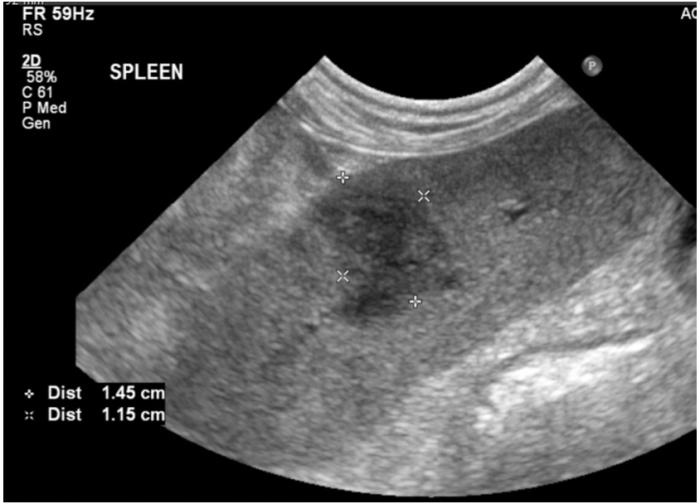

Se realizó ecografía abdominal ante la elevación de enzimas hepáticas y la sospecha de posible origen extracraneal de las convulsiones. El estudio, realizado por un especialista europeo en diagnóstico por imagen, evidenció:

- Nódulo esplénico hiperecoico, bien delimitado, de 1.4 × 1.1 cm (Figura 1).

- Glándula adrenal izquierda aumentada de tamaño (0,96 cm) con nódulo hipoecoico craneal de 1.2 cm

- Citología esplénica (PAAF): inflamación mixta con abundantes hifas fúngicas, tanto extracelulares como intracelulares (macrófagos) (Figura 2).